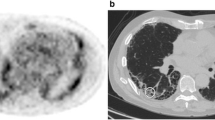

[18F]FDG PET/CT involved a PET-CT scanner (GE Discovery 690, GE Health-care, Milwaukee, WI, USA). All patients fasted for at least 6 h before the examination. The serum glucose levels were < 9 mmol/L. PET-CT images were obtained 60 min after injection of 4 MBq/kg [18F]FDG. We performed iterative construction with attenuation correction, scatter correction, variant point spread function compensation and time of flight. The time of the image acquisition at 60 min was 3 min per bed. The regions of interest were manually identified. A visual analysis described the regional distribution of FDG uptake. Quantitative analysis was then performed. The SUV mean and SUV max were obtained for the right and left lung. Hereafter, the SUV mean is the geometric mean of SUV mean for the left and right lungs and the SUV max is the geometric mean of SUV max for the left and right lungs. The whole lung was delineated by an automatic lung extraction available in Planet software (DOSIsoft, Cachan, France) (Fig. 1, outlined yellow area). The bronchi were not excluded. The uptake from liver mediastinum (including heart but excepting adenopathy) was manually excluded when needed. Figure 1 shows the representative regions of interest used for analysis in a control patient (at the top) and in IPF patient (at the bottom). The area outlined in yellow represents the lung volume. The area outlined in red represents the metabolic lung volume. The MLV was determined considering a threshold of 1, considering the normal lung SUV mean to be 0.5. This was determined by measuring the mean SUV in lung of normal patients. We then applied a safety margin by using a threshold of 1. Therefore, we ensured that the MLV contained no or very few normal lung voxels. The relevant PET-related variables were extracted for the MLV and the whole lung. The variables were the maximum SUV (SUV max) and average SUV (SUV mean), from which we derived the TLG [ie, the product of the MLV and SUV mean [23]].

All IPF patients showed increased [18F]FDG uptake as compared with controls, both in the quantitative and visual analysis. SUV mean and SUV max were higher for IPF patients than controls (1.0 ± 0.4, p < 0.00001, and 3.8 ± 2.5, p < 0.0001, respectively) (Fig. 2). SUV mean and SUV max did not differ between the right and left lungs (Table 2). The mean TLG was 1426 ± 1030 cm3 and mean MLV 950 ± 571 cm3. Increased pulmonary [18F]FDG uptake was predominant in sub-pleural areas and corresponded to honeycombing/reticulation areas.

To our knowledge, this is the second largest series of patients with IPF involving study with [18F]FDG PET and the first study to assess the usefulness of TLG and MLV in assessing IPF prognosis. [18F]FDG uptake was higher for IPF patients than controls (Fig. 1) and [18F]FDG uptake was positively correlated with disease severity (assessed by multiple indexes of lung function alteration and GAP stage). Furthermore, MLV and TLG but not SUV mean or SUV max were independent factors of progression-free survival.